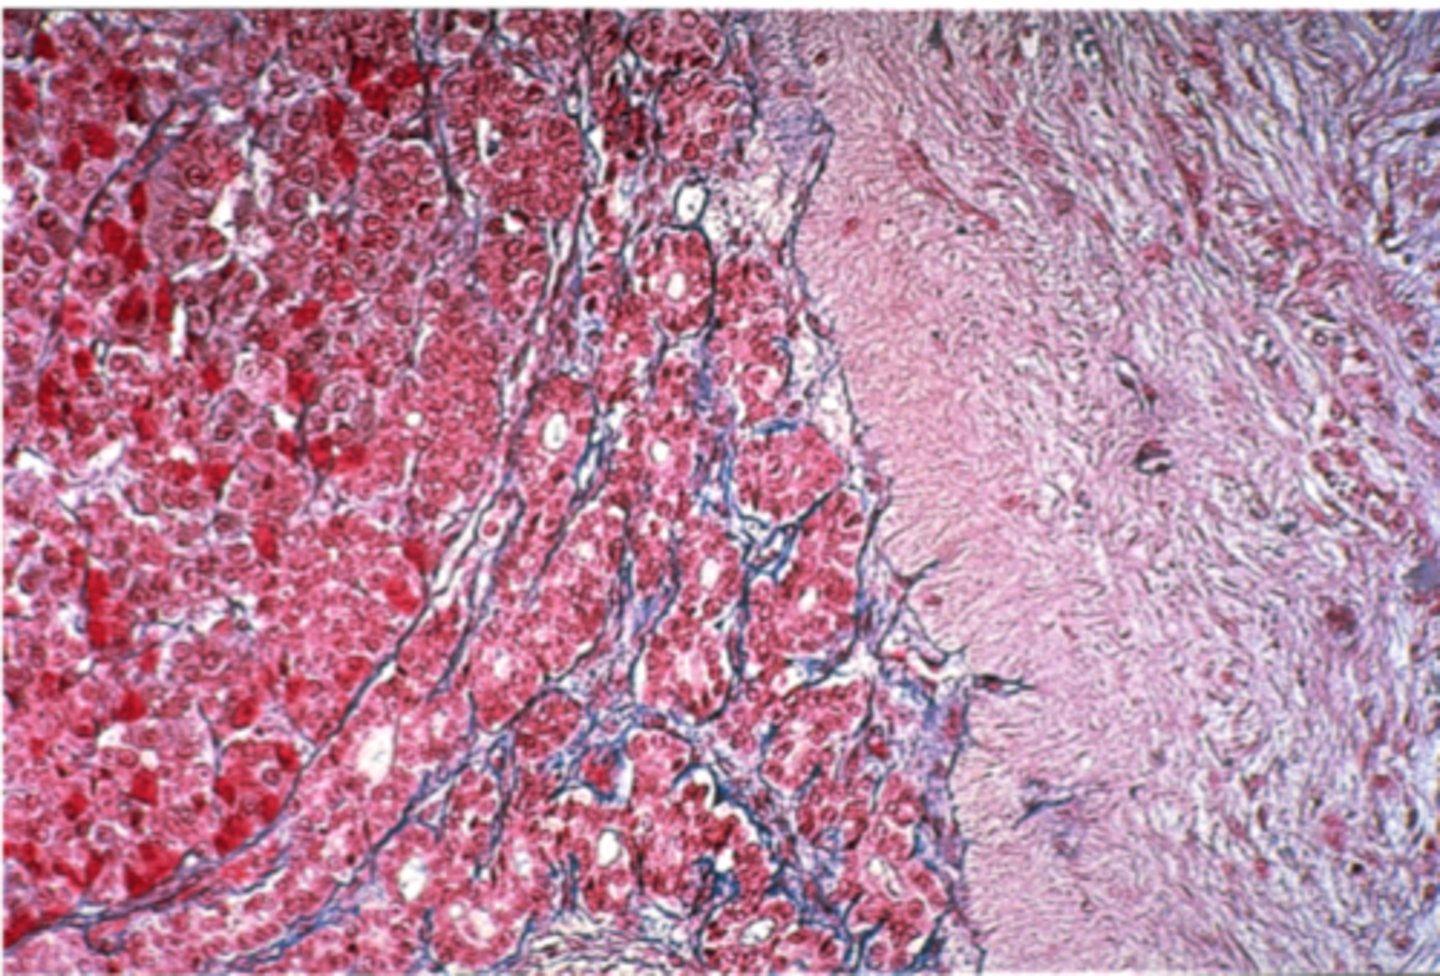

Liver

What is this?